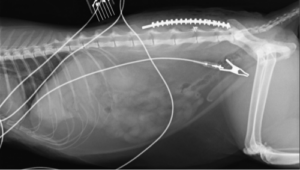

術前レントゲン;

コメント;

第5-6腰椎間でのずれが確認されます。VD像でも横方向のずれも確認されます。